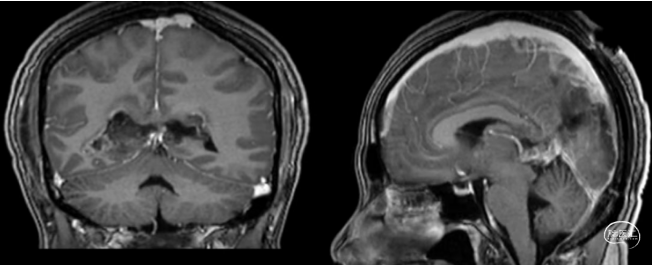

术前MRI

临床症状进行性加重,短期内出现头痛症状,影像学提示胼胝体压部占位,肿瘤紧邻三脑室顶后部、中脑顶盖、中脑导水管、四叠体池/脑深部引流静脉受压明显,占位效应重。

本例患者影像学上表现为累及胼胝体压部的典型的蝴蝶状胶质瘤,病变累及双侧半球,非对称分布。手术均用右侧顶枕叶造瘘+左侧纵裂入路,术中先后探查和分块切除大脑镰后部两侧的病变。大脑镰后部毗邻大脑深部静脉系统,需要尽可能避免损伤Galen静脉或下矢状窦等重要结构,左侧纵裂入路可能有利于实现更好的功能保护。位于胼胝体不同部位的蝴蝶状肿瘤,由于解剖基础和功能保护的需求,采取不同的入路,从而在尽可能保护脑功能的前提下安全切除病变。